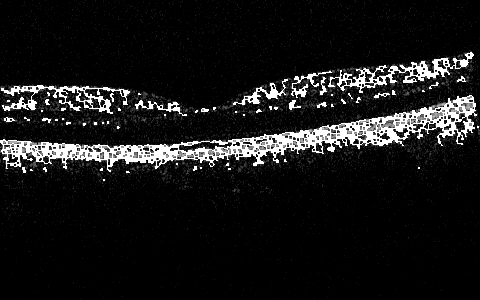

More interesting preliminary results include global 2D (2D at the moment, per slice, but will expand the window to 3D space next) processing that includes in one algorithm some subalgorithms that do preprocessing, skeletonizing, or filling/thinning, and active-contouring of the images from the Zhang-Suen transform. There are many of the options and configurable parameters to try, but already now the outlines of the ILM, IS/OS, RPE can be seen in a very draft debug mode in Figure 7, Figure 8, Figure 5, Figure 6, Figure 9, and Figure 10.

Figure 5: 2D Zhang-Suen Skeletonizing near Fovea

Refer to caption

Figure 6: 2D Zhang-Suen Skeletonizing of Slice 90

Figure 7: 2D Zhang-Suen Filling-Thinning-Contouring near Fovea

Figure 8: 2D Zhang-Suen Filling-Thinning-Contouring of Slice 90

Figure 9: 2D Zhang-Suen Filling-Thinning-Skeletonizing near Fovea

Figure 10: 2D Zhang-Suen Filling-Thinning-Skeletonizing of Slice 90